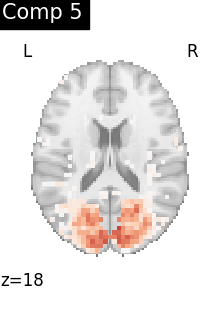

One plot of each component

for i, cur_img in enumerate(iter_img(dictlearning_components_img)):

plot_stat_map(

cur_img,

display_mode="z",

title=f"Comp {int(i)}",

cut_coords=1,

vmax=0.1,

vmin=-0.1,

colorbar=False,

)